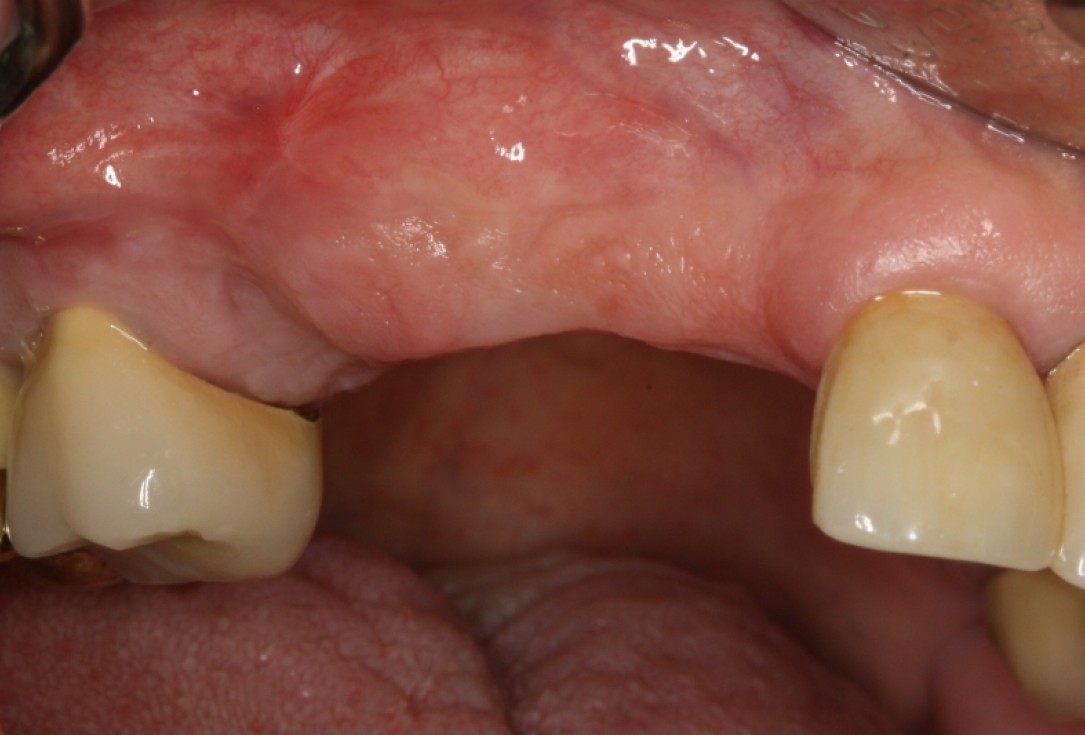

GBR and soft tissue augmentation with cerabone® and mucoderm® - H. Maghaireh & V. Ivancheva

Initial situation: missing teeth #11 & 12 and badly broken #21 root